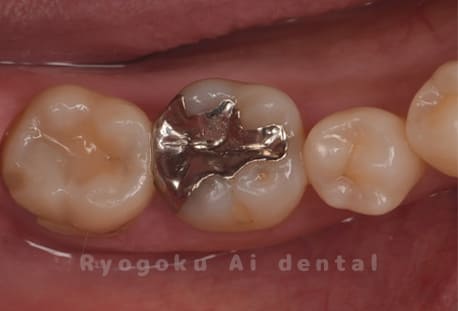

Case07

-

- 原因

- 虫歯

- 治療内容

- セラミッククラウン

- 治療費用

- 110,000円

銀歯が浮いた感じがする、と相談された患者さんです。銀歯を外し、虫歯治療を行い、セラミックの被せ物で治療を行いました。

<リスク・副作用>

過度の咬合や衝撃で割れることがあります。